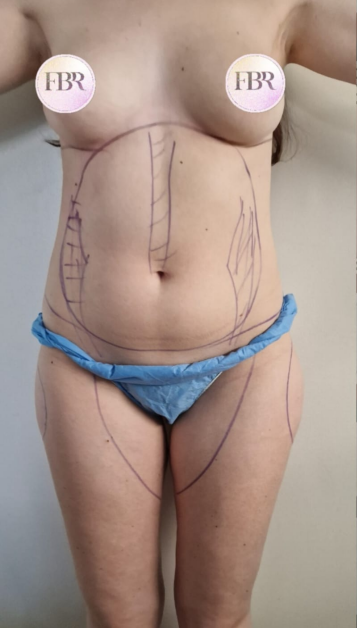

Découvrez les résultats de du lipofilling des fesses sur nos patients

AVANT

APRÈS

Autres résultats

Ces cartes sont cliquables : cliquez ou appuyez sur une carte pour ouvrir le cas en grand (même présentation AVANT / APRÈS que ci-dessus).